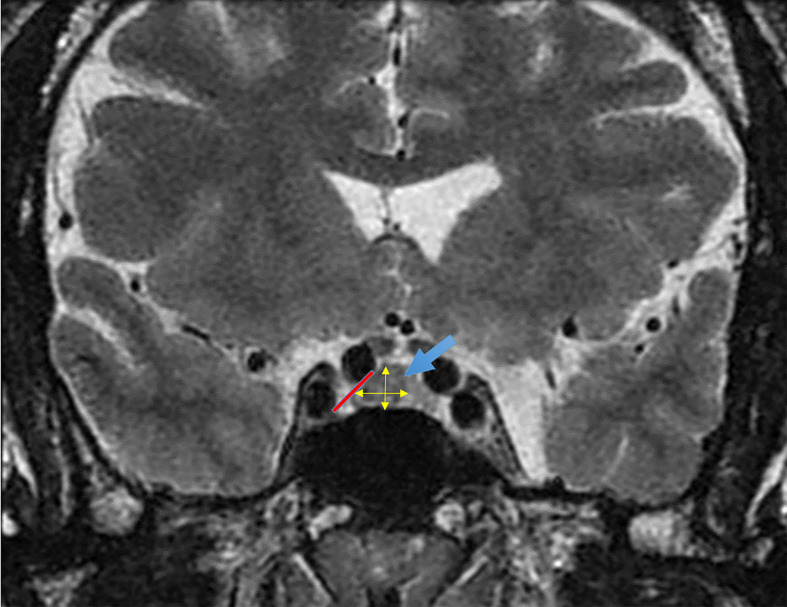

Background: Acromegaly is caused by a pituitary neuroendocrine tumor (PitNET) with excessive production of growth hormone (GH), leading to multisystem complications. Previous studies have identified predictors of disease persistence following surgery and poor response to medical treatment, including tumor size, vertical and horizontal extensions of the adenoma, hyperintensity in T2-weighted magnetic resonance imaging, granulation density, and pre- and postoperative GH and insulin-like growth factor 1 (IGF-1) levels.

Results: A total of 77 patients with acromegaly (42 men, 35 women) were included in this study. The mean age at diagnosis was 42 years (SD: 12), with a mean disease duration of 9.9 years (SD: 7.2). The mean pituitary tumor volume was 4358 mm³ (SD: 6291, interquartile range [IQR]: 13602). Patients with controlled acromegaly had a mean PitNET volume of 3202 mm³ (SD: 4845, 95%CI: 621-5784) compared to 5513 mm³ (SD: 7447, 95%CI: 1545-9482) in the uncontrolled group (P = 0.15). A PitNET volume exceeding 3697 mm³ was associated with a higher likelihood of requiring third or fourth-line therapy (50% vs 36%; P = 0.03).